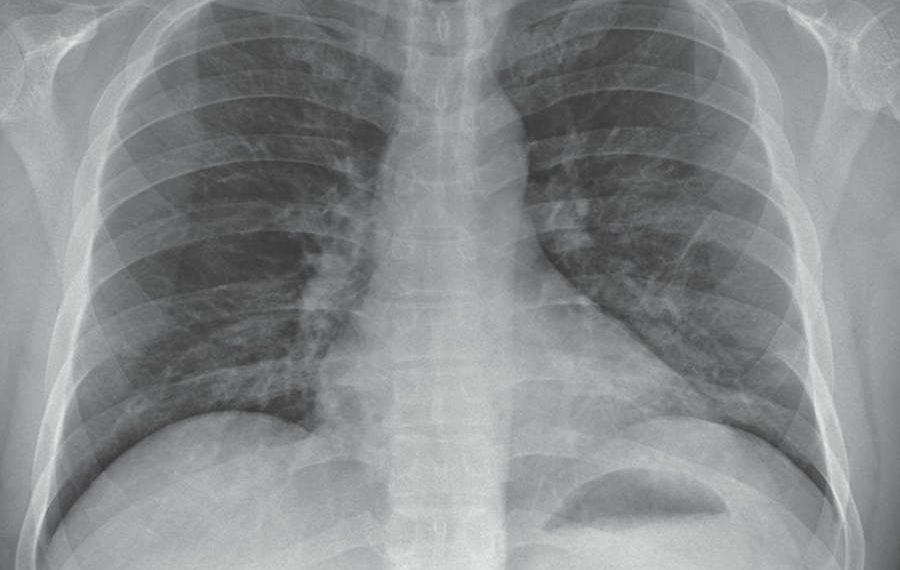

Deja, principalmente, afectaciones pulmonares, pues la gente se agita con facilidad.